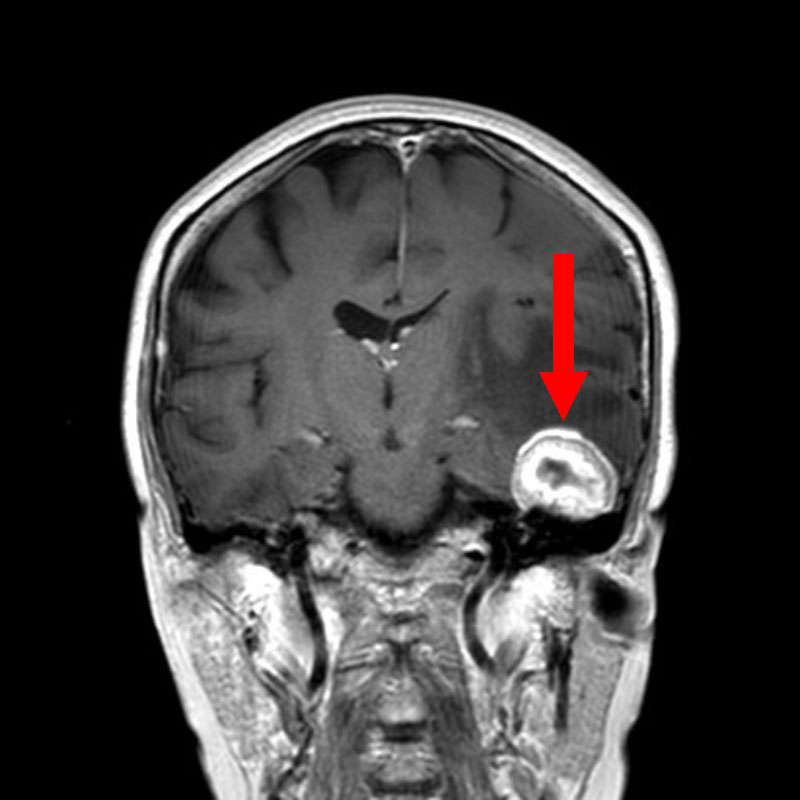

右頭頂葉腫瘍

頭蓋内腫瘍摘出術

No.’25_108 手術前1

No.’25_108 手術前2